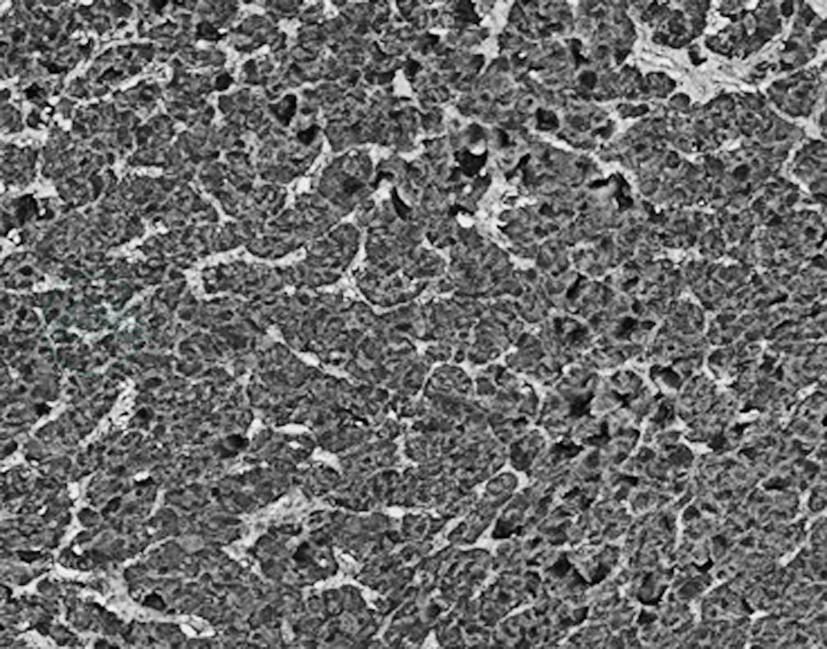

肾上腺嗜铬细胞瘤直径常小于100mm,多为30~50mm,呈圆形或椭圆形,极少数为哑铃型,有包膜,瘤体切面为黄白色至红棕色,暴露于空气中可变为黑色。嗜铬细胞瘤的名词来源于肿瘤组织浸润在铬盐(嗜铬反应)或其他弱氧化剂中发生的颜色变化。肿瘤内血管丰富,大的肿瘤常有出血、坏死、囊性变,钙化少见。巨检肿瘤与邻近肾上腺之间界限清楚,但显微镜下肿瘤与邻近肾上腺无真正的包膜,肾上腺通常受压或混合在肿瘤中。肿瘤可有纤维假包膜或扩展到肾上腺被膜中,邻近皮质的边缘可不规则,肿瘤细胞与皮质细胞混合性生长。显微镜下肿瘤呈特征性巢状(细胞球Zellballen)和/或梁状结构生长为主,亦可见到弥漫性或实性结构,细胞间富于血管。肿瘤细胞具有细颗粒状的嗜碱性或嗜双色性胞质,细胞核圆形或卵圆形,核仁明显,部分出现假包涵体结构。瘤细胞可有显著多形性,巨核及深染的细胞核常见。但和其他内分泌肿瘤一样,并非恶性的表现,肿瘤内亦可见孤立的神经节细胞(图1)。免疫组化嗜铬细胞瘤CgA阳性(图2),肿瘤中的支持细胞(位于细胞球周围)S-100蛋白阳性。恶性嗜铬细胞瘤的直径较良性肿瘤更大、坏死更多。但事实上除肿瘤出现转移(不包括肿瘤广泛或局部浸润到邻近器官或大血管,而必须出现在原来没有嗜铬组织的部位)外,并无可靠的形态学标志,没有一个组织学特征能作为独立指标确定肿瘤是否具有临床侵袭性行为。转移的主要部位常为肝脏、骨骼、淋巴结、肾和肺部。

图2免疫组化肿瘤细胞嗜铬素阳性表达